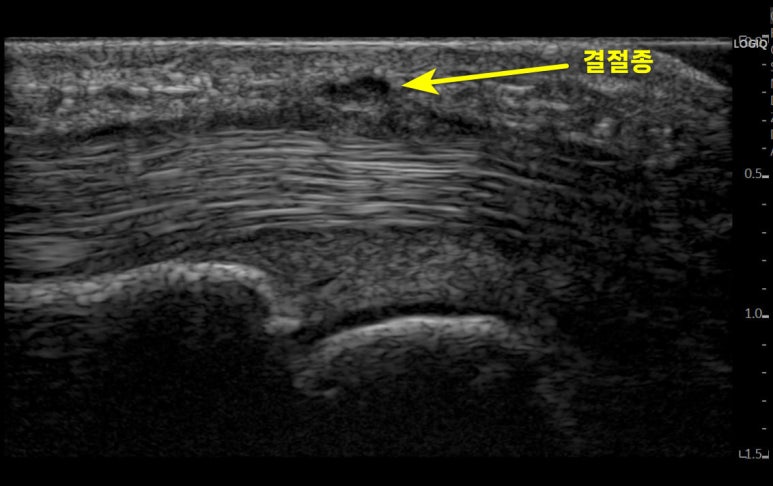

자세한 상태를 진단하기 위해

경혈 초음파로 검사해보았습니다.

경혈 초음파로

침 놓을 혈자리를 살펴보니

A1 도르래가두꺼워진 상태였습니다.

정밀하게 체크해보니

힘줄 주변 집도

어둡게 부어있고

A1 도르래(활차)에

물혹(결절종)도 확인되었습니다.